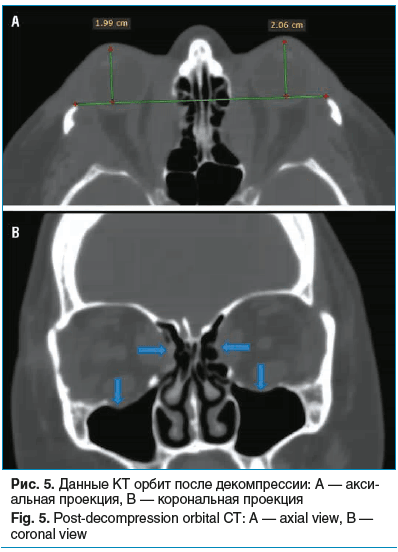

Контрольная КТ орбит подтвердила уменьшение экзофтальма до значений OD — 19,9 мм, OS — 20,6 мм, что составило регрессию на 6–7 мм. На томограммах визуализируются костные дефекты наружных и частично внутренних стенок орбит (рис. 5).